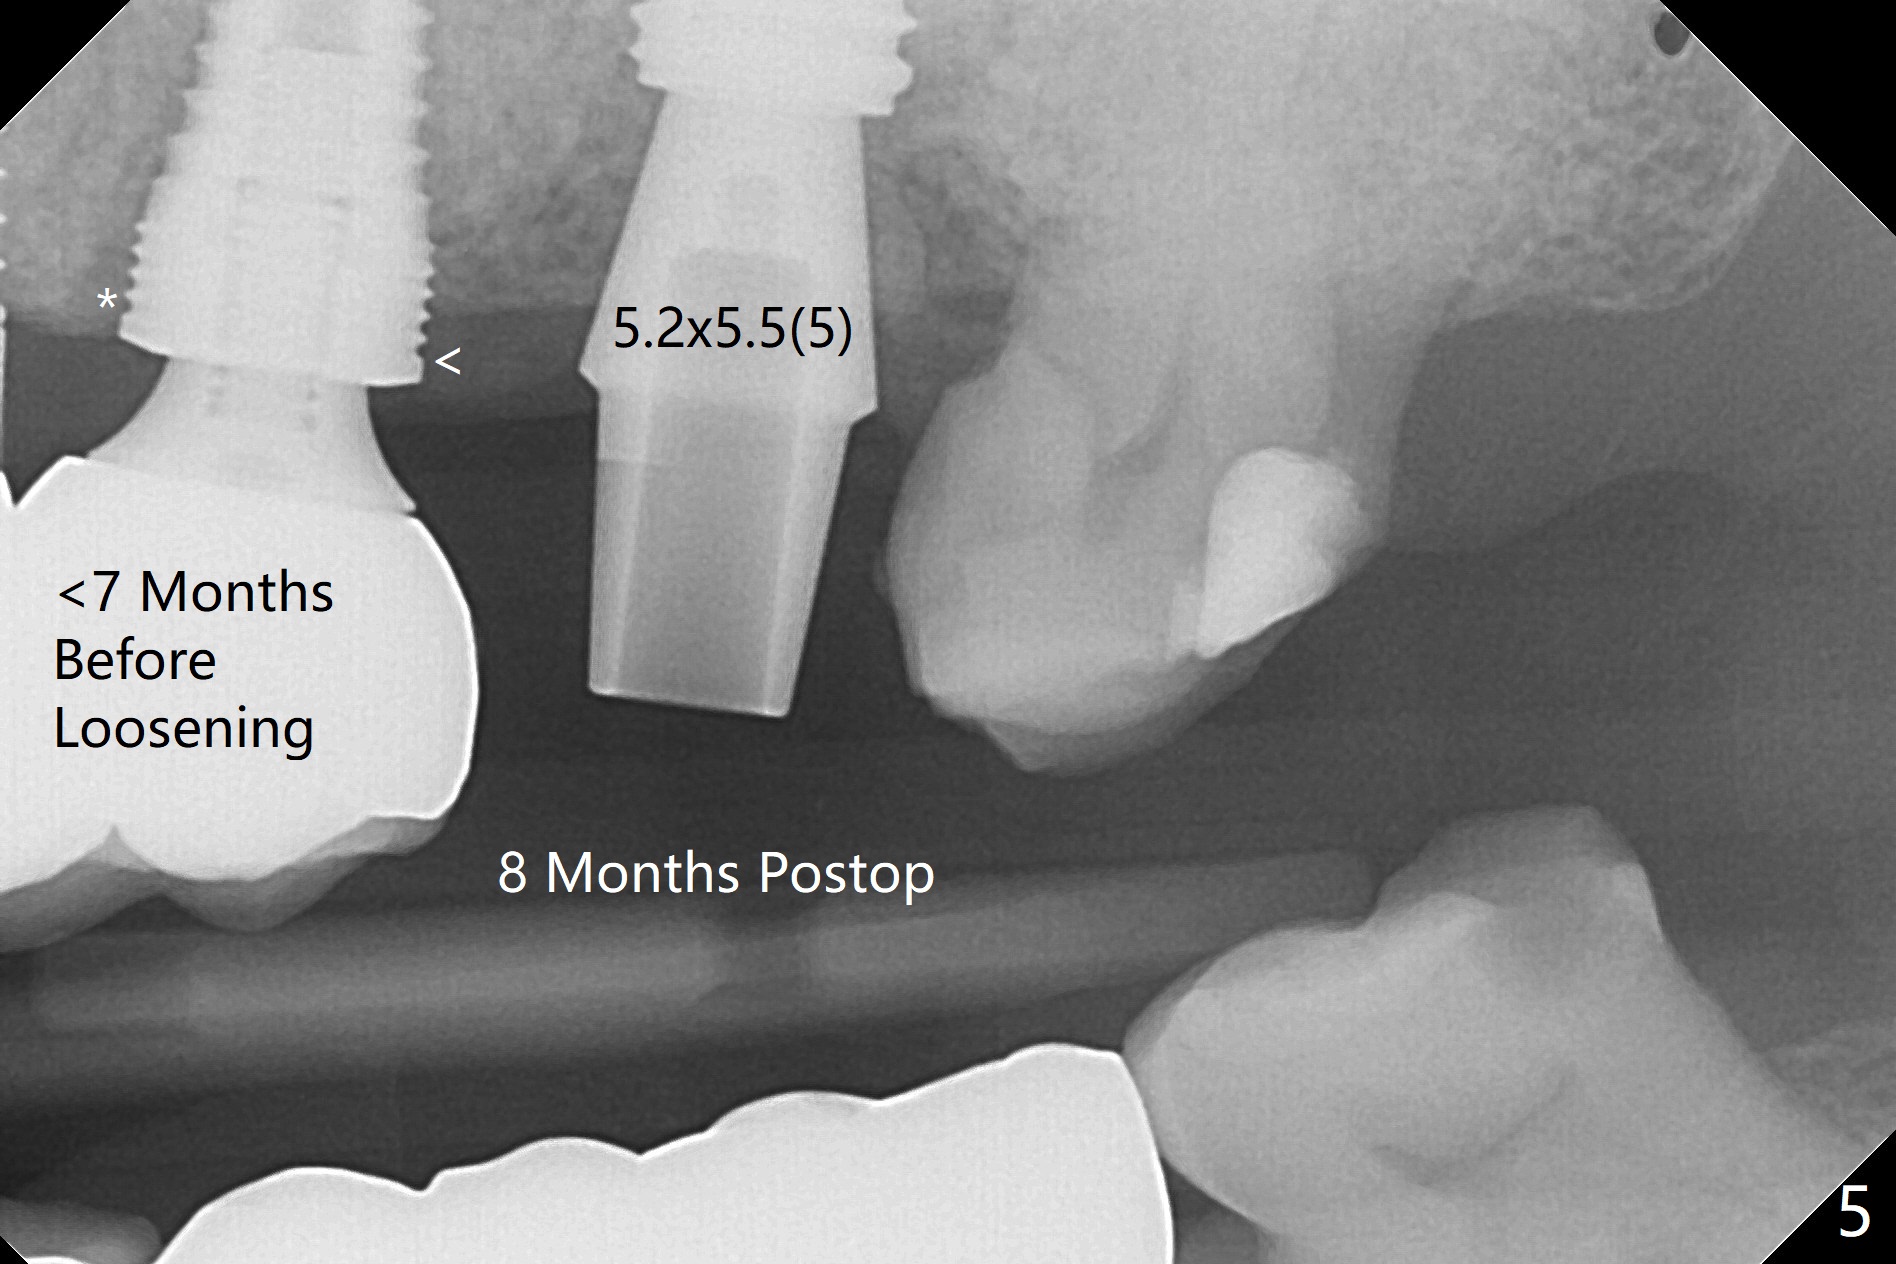

Due to low bone density post large implant (7 mm in diameter) removal with bone graft at #15, osteotomy with guide is underprep (last drill: 3.5x10 vs. 4.5x10 mm (design)). When a 4.5x10 mm dummy implant is placed at the beginning of the 1st line (10.5 mm offset), the torque is ~ 15 Ncm. As a 5x8.5 mm final implant is being placed, the torque increases to 30 Ncm (Fig.1,2) with apparently incidental sinus lift (Fig.3 arrows). The implant remains in place with a healing abutment 2 months 9 days postop (Fig.4). Healing abutment is changed from 5.5x6 to 6.8x5 mm 4.5 months postop when #16 MO composite is redo. There is bone loss at #14 mesially (Fig.5 *) with microthread exposure (<) less than 7 months before loosening.